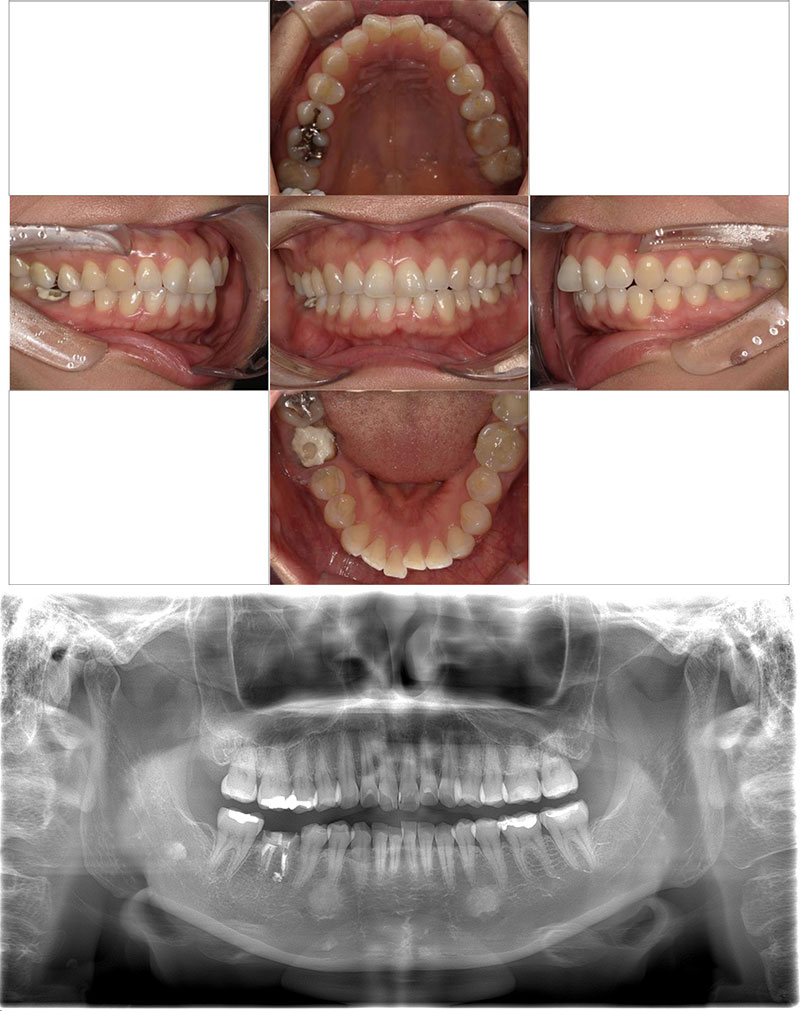

治療前

Before

治療後

After

年齢 10

性別 男児

主訴 下あごが出ている